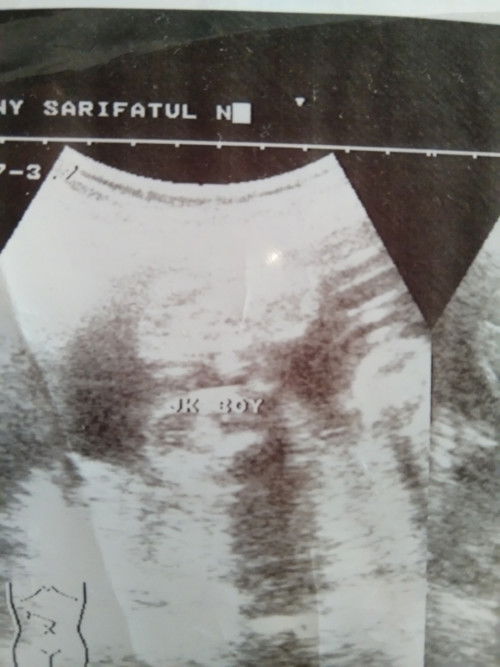

# #mohonbantujawabbunda

sedang mengandung

gak ada yg bisa baca hasil USG kecuali dokter itu USG dimana, btw? kok burem banget ya